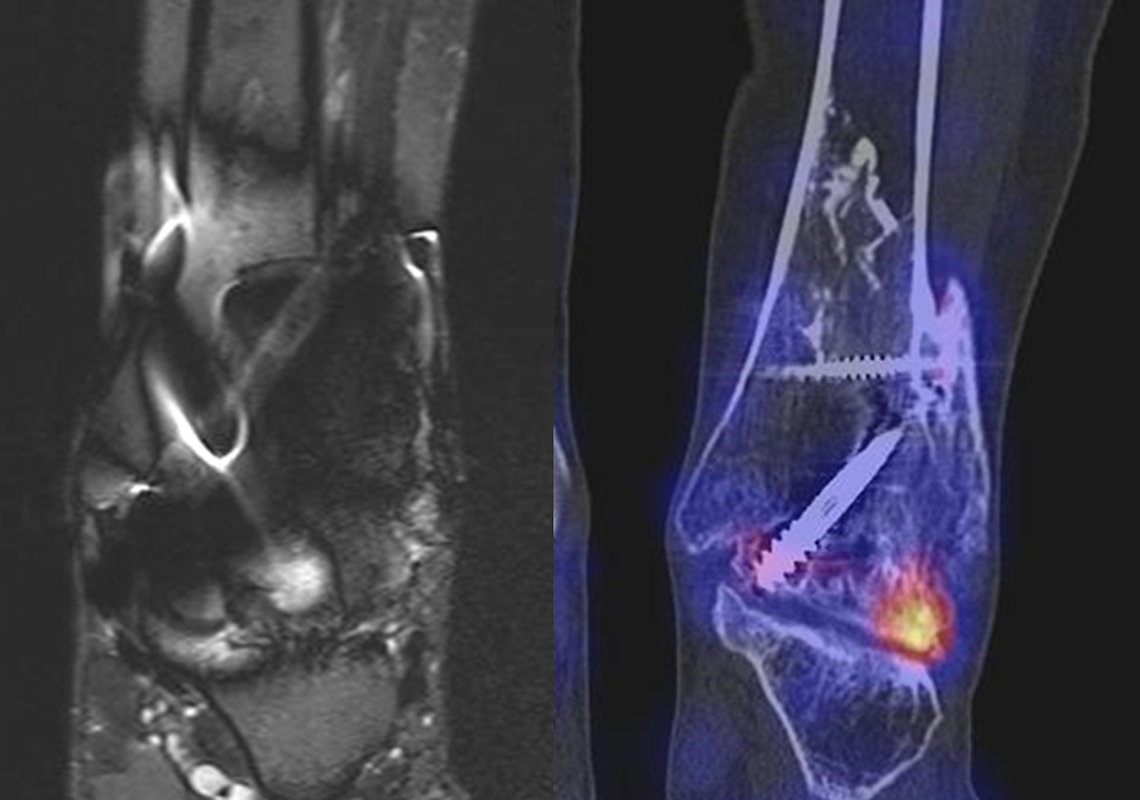

Abbildung 8.6. a bis f: Patientin mit Z. n. Talusfraktur vor 2 Jahren, welche mit zwei Schrauben osteosynthetisch versorgt wurde. Seither progrediente Schmerzen im linken Fuß. Ein MRT 8 Monate vor der SPECT/CT-Untersuchung war nicht eindeutig bzw. nicht wegweisend. Im SPECT/CT aktivierte posttraumatische osteochondrale Läsion talusseitig im linken unteren Sprunggelenk mit einem abgrenzbaren Ossikel bis 5 mm Größe und angrenzenden arthrotischen Veränderungen. Reizlose Schrauben im linken Talus.

Abbildung 8.5.a bis f: Patientin mit anhaltenden Schmerzen bei Z. n. Hallux valgus-OP vor 8 Jahren. Im MRT 7 Wochen vor der SPECT/CT kein wegweisender Befund bei auch deutlichen Artefakten durch Metallabrieb. Im SPECT/CT Nachweis von arthrotischen Veränderungen im Metatarso-Sesamoid-Gelenk mit einem intraossärem Ganglion im Köpfchen von

Os metatarsale I.